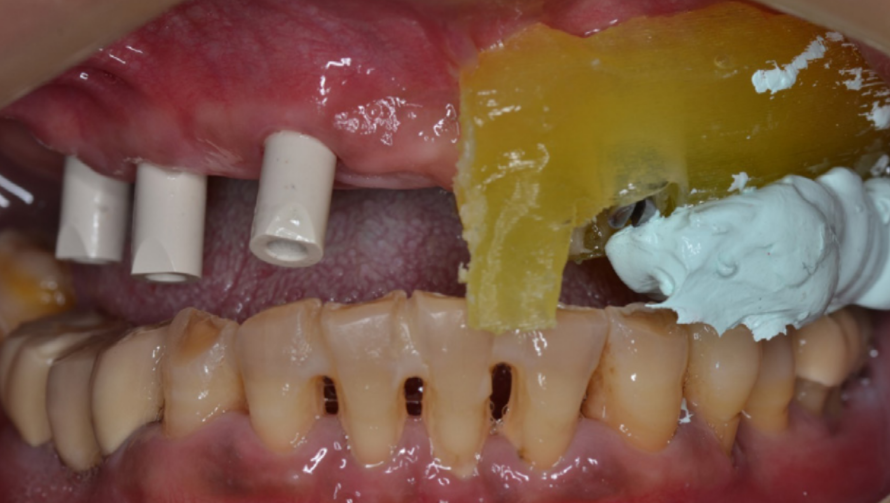

Щоб правильно розмістити імпланти, протягом процесу розробки з хірургічного шаблону було видалено всі зуби, за винятком 2 центральних різців та 2 перших молярів. (зображення 4)

Ці зуби були залишені, щоб підтримати встановлений прикус при змиканні імплантів.

4

Під час проведення процедури хірургічний шаблон було міцно стиснуто пальцями до піднебіння.